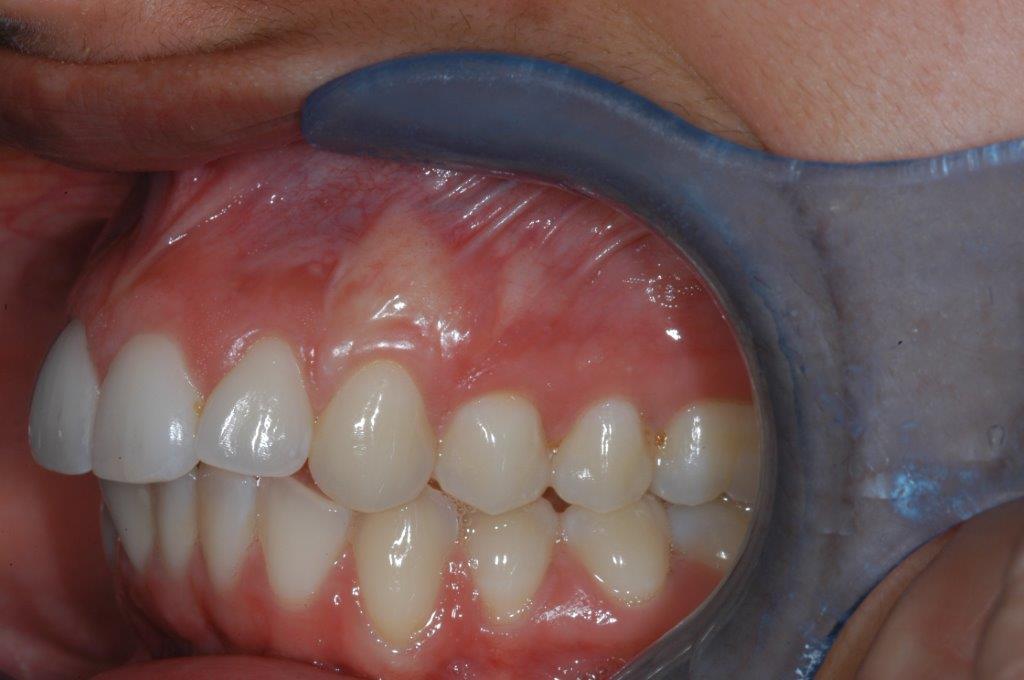

This patient experienced many areas of gum recession, primarily on the upper and lower front teeth. This patient's own tissue was used to correct the problem.